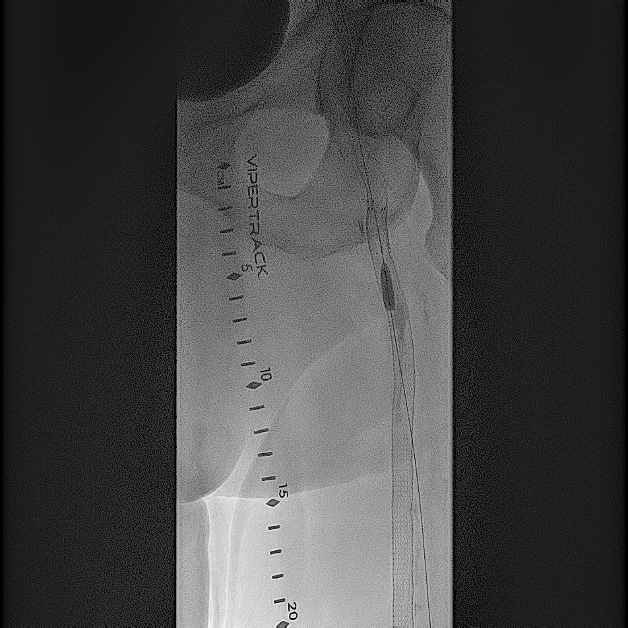

Based on his comorbidities, history of recurrent stenting of the left SFA, and an occlusion of the SFA over 200 cm, he was deemed to be an appropriate candidate for percutaneous transmural arterial bypass (PTAB). However, in order to establish long-term patency, we proceeded to gain posterior tibial artery access to identify a 3-vessel runoff (Figure 2). With this information, using the outline of the stents in left SFA and using a 0.018-in Glidewire Advantage (Terumo) and a 0.018-in Rubicon catheter (Boston Scientific), we were able to obtain access into the left profunda femoral artery (Figure 3). Despite multiple-balloon angioplasty, the recoil within the left common femoral artery (CFA) left little option but to place a 7.0-mm Eluvia stent (Boston Scientific), which was overlapped with the proximal stent in the left SFA (the profunda femoral artery was patent after balloon angioplasty; Figure 4).